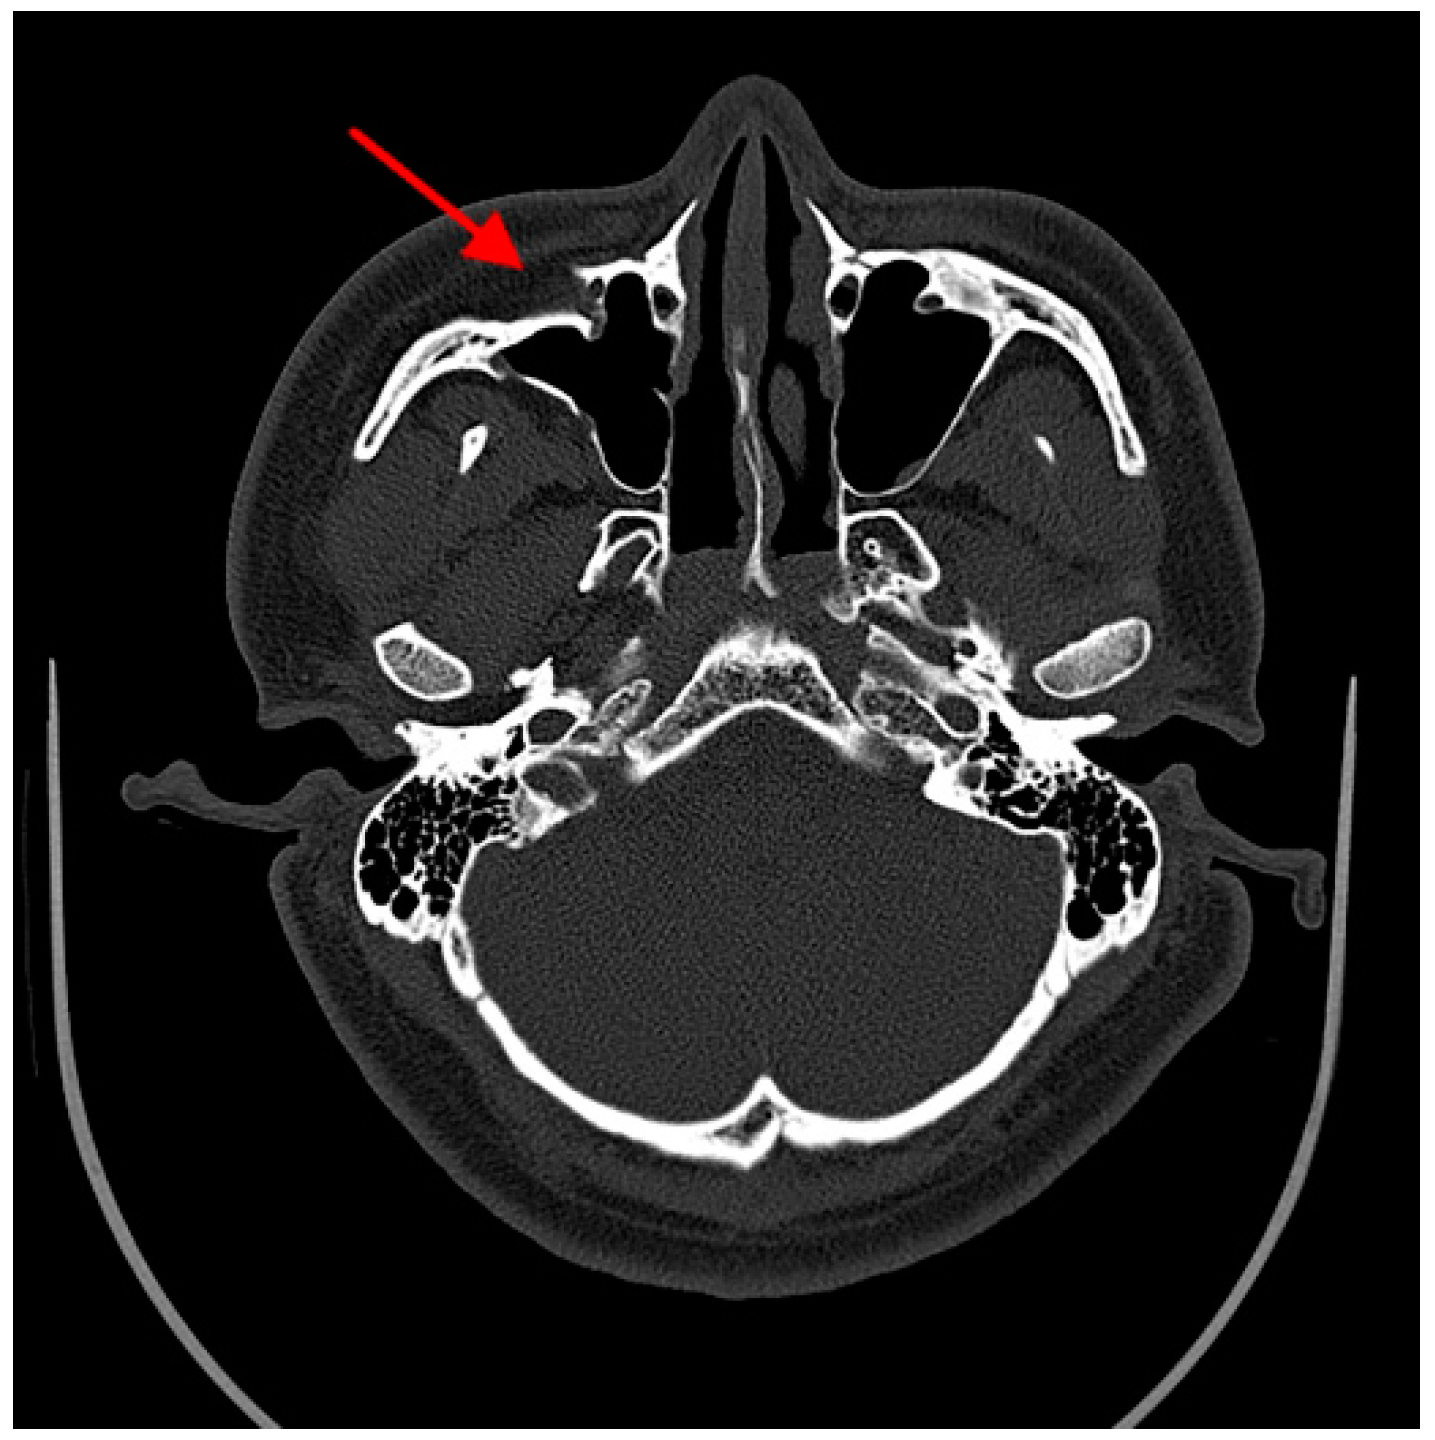

Maxillary sinus wall fracture reduction evaluation was based on Ellis’s classification [29]. Any asymmetry on the images more than 2 mm in magnitude was considered an imperfect reduction of the fracture on the CT axial scan image (Figure 3).

Figure 3.

Imperfect reduction. Axial scan through the superior portion of the maxillary sinus and zygomatic arch. The arrow indicates the imperfect reduction of the maxillary sinus wall.